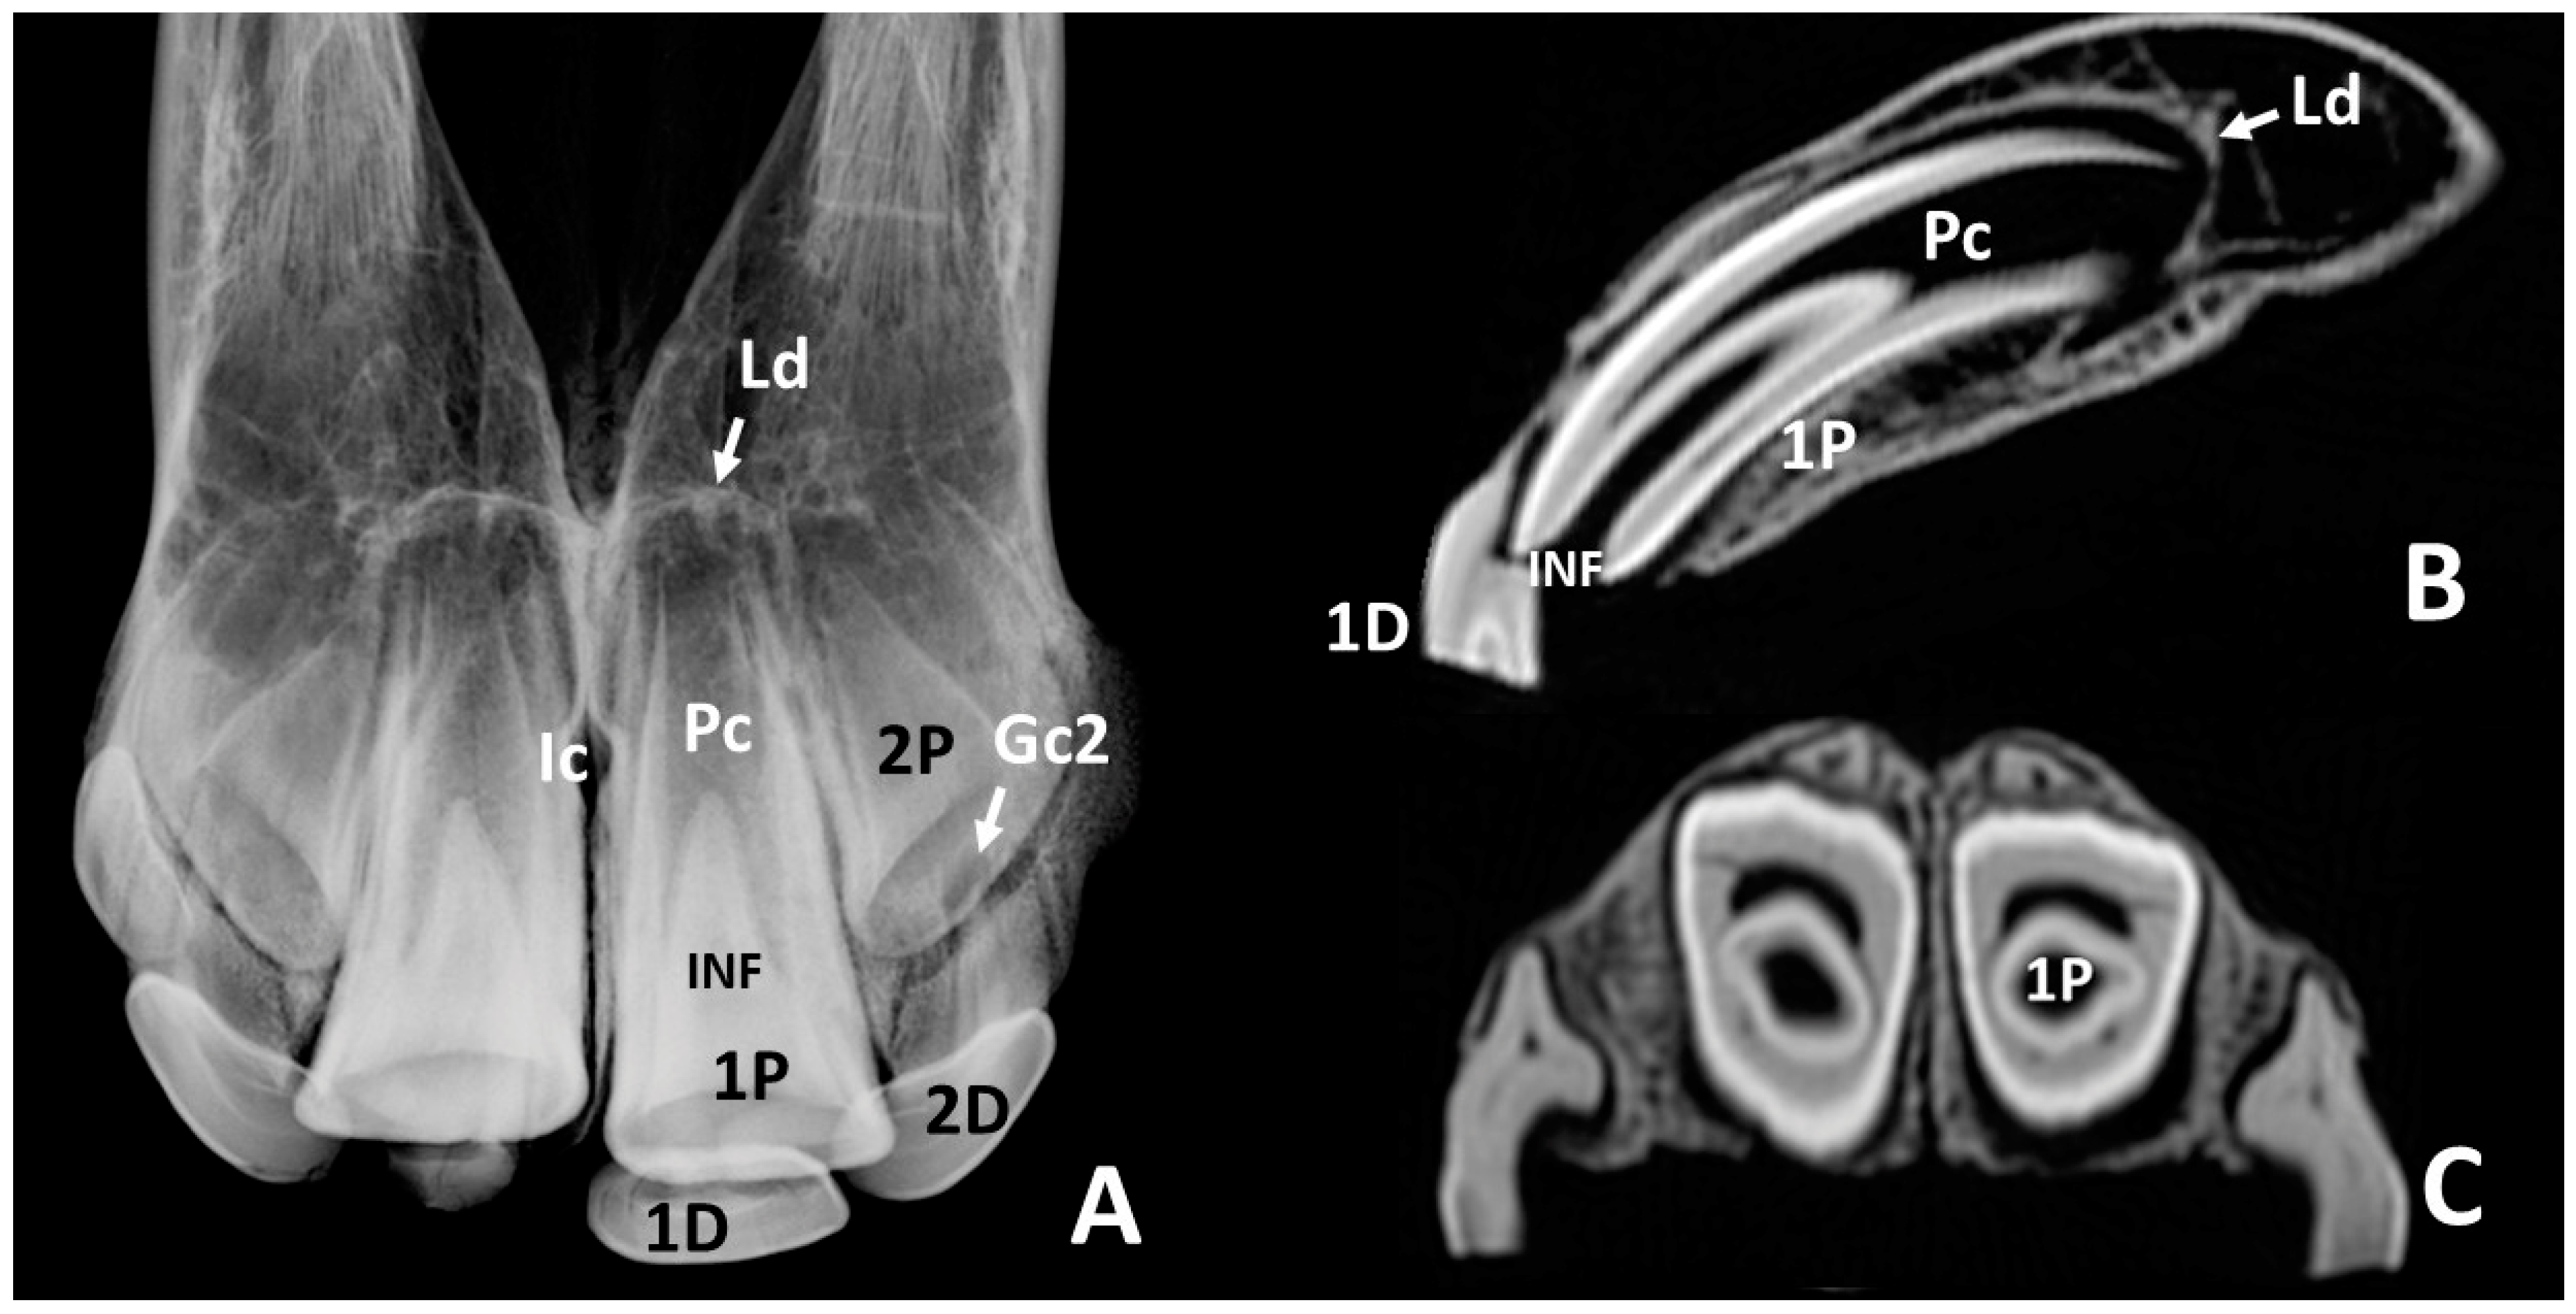

3.2. Radiographic and CT Studies

4.1. Deciduous Incisors: Radiographic and CT Studies

4.2. Permanent Incisors and Alveoli: Radiographic and CT Studies